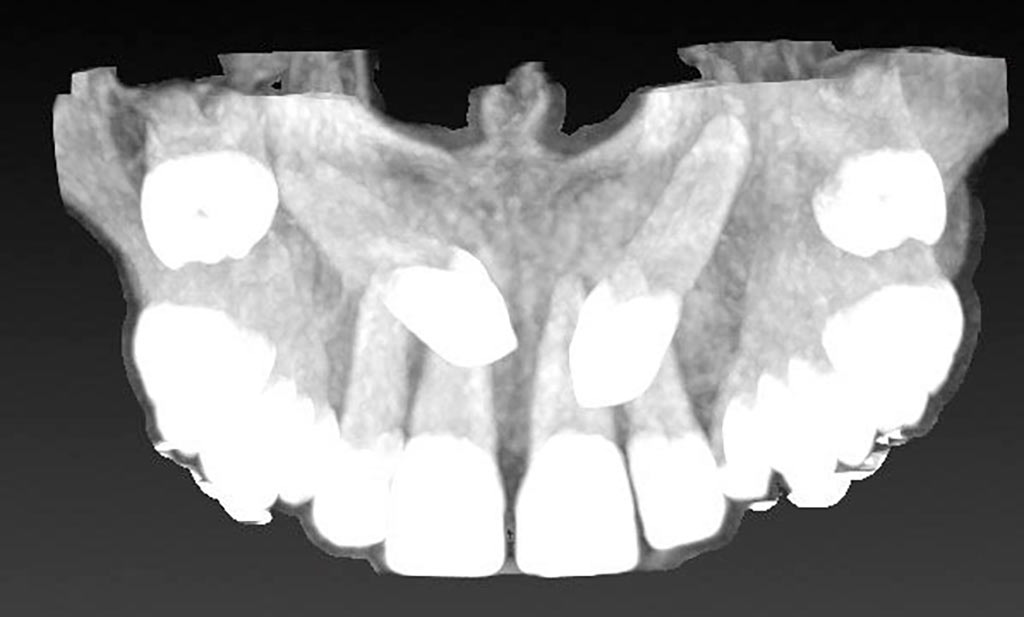

Tracción de canino con k9